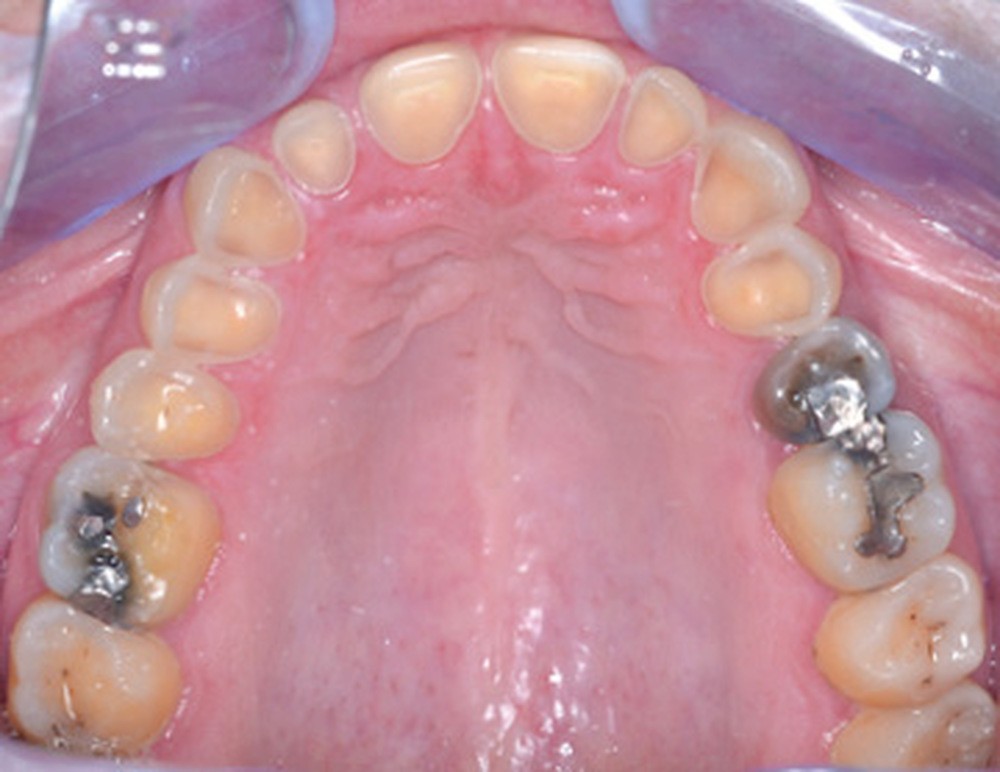

Mme V. est adressée au cabinet dentaire pour une réhabilitation de son sourire. À l’examen clinique, elle présente des usures sur l’ensemble de son maxillaire (fig. 17 et 18). Après évaluation du décalage OIM-ORC, une position de référence en relation centrée avec une dimension verticale augmentée est enregistrée. Pour valider cette position, il est demandé au laboratoire de réaliser un wax-up virtuel. Ce dernier est validé puis transféré en bouche pour essayage (fig. 19 et 20).

Ce mock-up est équilibré puis transformé en projet provisoire pour trois mois afin de s’assurer de la stabilité, du confort masticatoire et de l’esthétique. Au terme de ces trois mois, une empreinte de la situation est réalisée ainsi que l’enregistrement de l’occlusion ; enfin les secteurs postérieurs sont préparés pour recevoir des overlays. L’ensemble des informations (position et forme) est repris au sein du laboratoire pour dessiner les prothèses d’usage. Ces dernières seront produites par usinage, puis maquillées avant d’être envoyées au cabinet pour assemblage par collage sous champ opératoire (fig. 21 à 23).